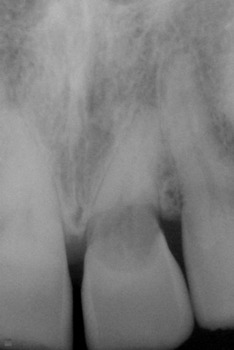

Reabsorción Externa

La reabsorción externa es la pérdida de tejido dental desde el exterior del diente hacia adentro, a menudo como resultado de un trauma o infección.

Los pacientes pueden no tener síntomas hasta que el diente se afloje.

El tratamiento incluye la eliminación de la causa y, a veces, un tratamiento de conducto. En casos severos, puede ser necesario extraer el diente.